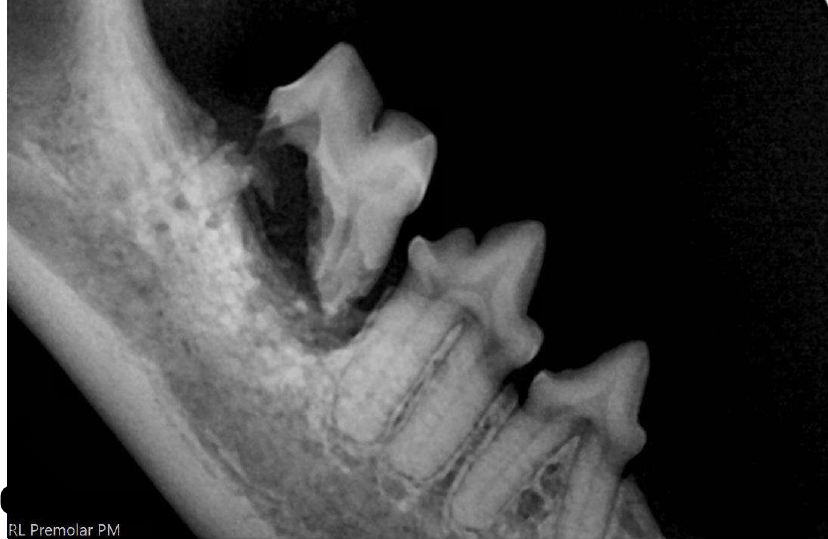

• Full Oral Exam and Radiographs (X-rays): X-rays are crucial for identifying painful problems beneath the gum line, such as broken roots, abscesses, or severe periodontal disease.

Resorption of Tooth Roots Found during Radiographs